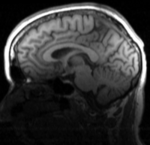

2. set T1_n4 as background and new DTI_Xf2 volume as foreground

3. Set fade slider to see DTI overlay onto the T1 image. You should see something similar to the animated gif shown in the result section below.